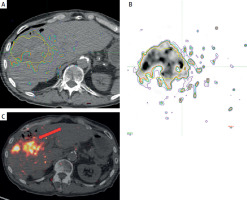

Figure 2

MIM software dosimetry analysis. Red arrow indicates absorbed radiation dose on post-Y90 PET/CT imaging, demonstrating its proximity to the colon

After multidisciplinary review, the decision to perform ablative RL with Y-90 resin microspheres (SIR-Spheres) was made. Pre-treatment work-up was performed and a dose of 500 Gy was planned for the tumor based on the partition model. Post-treatment dosimetry, performed using MIM Sureplan software, confirmed a mean absorbed dose of 463 Gy to the tumor, 215 Gy to the 5 mm margin, and 122 Gy to the 10 mm margin (Figure 2).